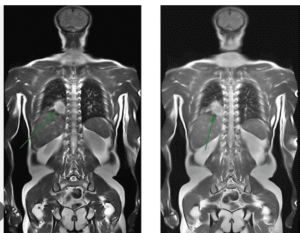

Hệ thống chụp CT 128 lát cắt – Đột phá trong chẩn đoán sớm

- Phát hiện siêu nhỏ: Nhận diện các nốt phổi bất thường chỉ từ 2-3mm.

- An toàn vượt trội: Kỹ thuật chụp CT liều thấp (Low-dose CT) giảm bức xạ đến 5 lần so với CT truyền thống.

- Tốc độ cực nhanh: Độ phân giải cao, hình ảnh 3D chi tiết, giúp bác sĩ không bỏ sót bất kỳ tổn thương nào.